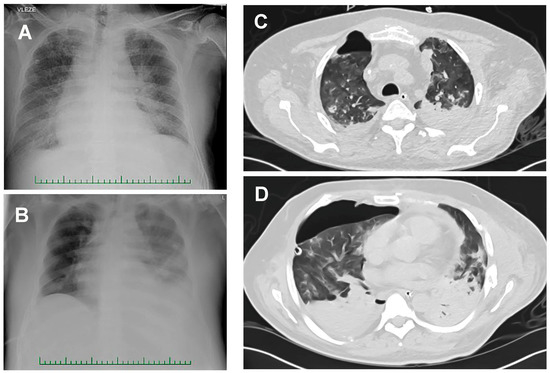

3.4. Pseudomonas aeruginosa in COVID-19-Associated Pneumonia